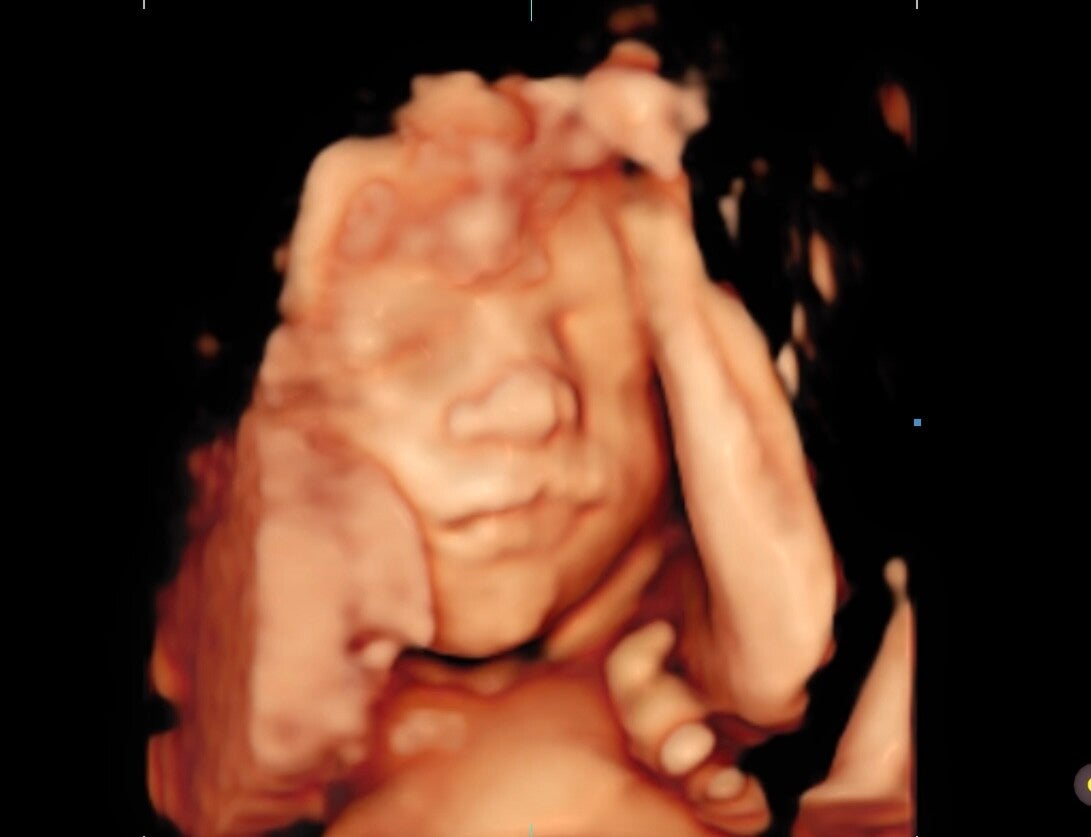

3D ECHO

Bij een 3D echo is jou baby in stille kleurbeelden zichtbaar met diepte in de beelden. De techniek die wordt gebruikt werkt hierbij hetzelfde als bij de 2D echo’s. Door de nieuwste technologie worden er meerdere 2D echo’s tegelijkertijd gemaakt en daardoor kunnen veel nieuwe systemen deze beelden omzetten en opbouwen tot een 3D afbeelding van de baby.

De kwaliteit van het beeld is afhankelijk van een aantal factoren. De ligging van de placenta en beweeglijkheid van het kindje is een belangrijke factor evenals de hoeveelheid vruchtwater. Wij adviseren een 3D/4D echo te doen vanaf de 25e t/m de 30e week in de zwangerschap. De baby ligt dan in een voldoende hoeveelheid vruchtwater en heeft genoeg onderhuids vetweefsel. Als je eerder of later een 3D/4D echo wilt kan dit natuurlijk ook. Zodra de baby is ingedaald kunnen wij geen pretecho's meer maken.

De ligging van de placenta is voor een pretecho erg belangrijk. Als jouw placenta aan de voorzijde ligt, raden wij aan om rond de 27 weken of eerder te komen voor een 3D/4D echo. Dit raden wij aan omdat de baby vaak tegen de placenta aan gaat liggen waardoor wij de baby niet goed op beeld kunnen krijgen, of een wazig beeld krijgen.